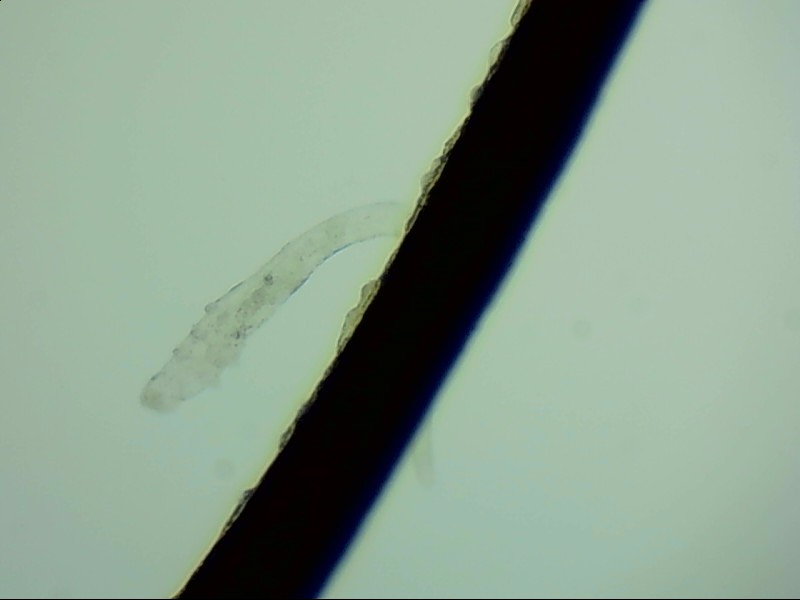

小張是一位程序員,長時間對著電腦,感覺眼干、有異物感在所難免。最近他除了眼干、難受,還發(fā)現(xiàn)眼睛發(fā)癢,掉落的睫毛上還會帶著絲狀的分泌物。剛發(fā)現(xiàn)時小張并沒有放在心上,但當他在屏幕上看到睫毛上的螨蟲時,他的心里一陣后怕,“原來我的睫毛上長著這么可怕的東西。”

螨蟲怎么會爬到睫毛里?廈門眼科中心蠕形螨性瞼緣炎門診張麗穎博士后介紹,人體螨蟲主要有兩種,一種是皮脂螨,主要寄生于皮脂腺和瞼板腺內(nèi);另一種是蠕形螨,“住”在睫毛毛囊里,晚上從毛囊里爬出來,白天躲在毛囊里產(chǎn)卵。

據(jù)介紹,這種疾病確診主要通過觀察睫毛里的螨蟲數(shù)量聯(lián)合瞼緣及眼表情況共同診斷。一般而言,如果12根睫毛里,有2條或是超過2條的螨蟲就可以被確診。如果檢查確實發(fā)現(xiàn)較多的蠕形螨感染,建議加上抗螨治療。張麗穎說,發(fā)現(xiàn)眼睛干澀、發(fā)癢,不要自行用藥,建議到醫(yī)院就診。如果長期反復(fù)多發(fā)霰粒腫,要考慮是否存在蠕形螨感染。